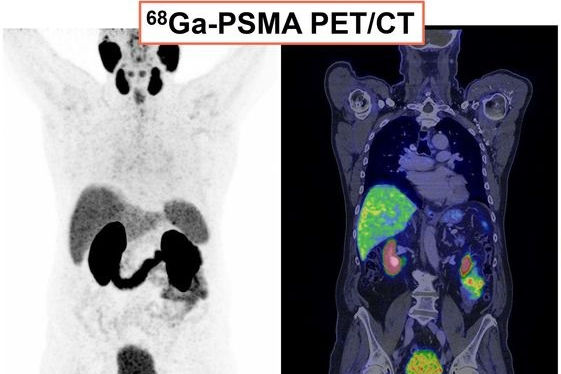

Axial views of exemplary case studies in which additional PSMA PET/CT changed prostate cancer (PCa) management. (A–D) A 68-year-old man with isolated PSA elevation had no tumor-suggestive findings on mpMRI (A and B), but they were high suggestive of PCa on PSMA-PET/CT (C). After radical prostatectomy, 22-mm index tumor identified on PSMA- PET/CT was confirmed with Gleason score of 7a (D). Reviewers without PSMA-PET/CT information (MRI-only pathway) recommended continued PCa screening, whereas reviewers with PSMA PET/CT knowledge suggested active treatment. (E–H) A 72-year-old man with PSA of 9.1 ng/mL and suggestive prostate palpation had highly suggestive PCa lesion on both mpMRI (E and F) and PSMA-PET/CT (G). PSMA-PET/CT also detected two small osseous metastases in left ilium (H) and sacrum. Management recommendations varied: local therapy (surgery or radiation) without PSMA PET/CT knowledge versus androgen deprivation therapy and radiation for primary tumor and metastases with PSMA-PET/CT knowledge.Journal of Nuclear Medicine